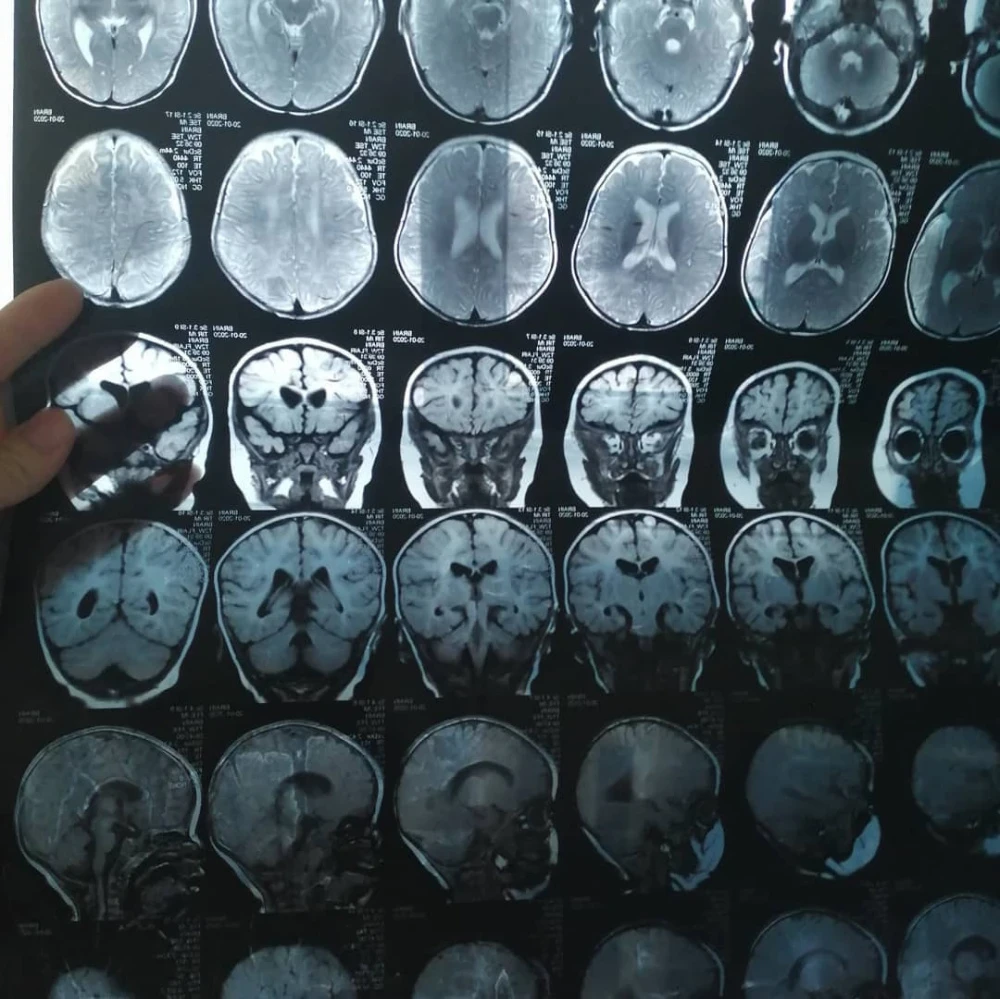

Бегимайдын кызынын бир нече татаал диагноздору бар, ага жардам керек.

Айкол Бишкекте буттун бурамасынын деформациясын оңдоо үчүн эки операциядан өттү, бирок, тилекке каршы, каалаган жыйынтыкка жеткен жок.